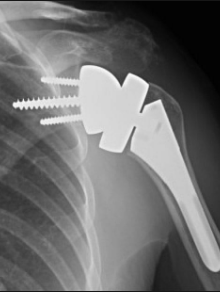

Prothèse anatomique

Elle est proposé devant une arthrose centré avec des tendons intacts